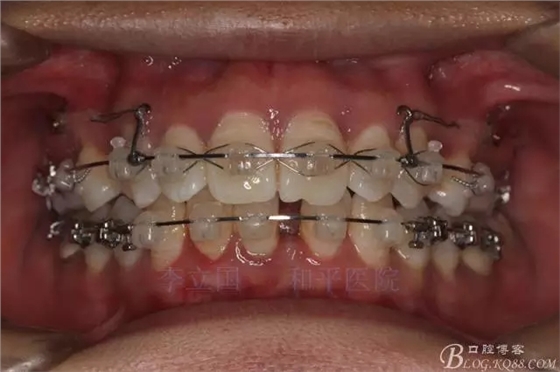

2.Damonclear排齊整平。

3.微種植支抗內(nèi)收上下前牙。

3.上頜應(yīng)用支抗釘。表麻下在56牙槽間隔植入,注意因使用的為鈦合金釘,一直保持植入角度與骨面成60度角,不要垂直植入再改變角度。要求即刻加載,即刻加載力值2盎司。

4.使用長牽引鉤,使牽引力接近上頜骨阻抗中心,防止上頜骨的順時針旋轉(zhuǎn)。

5.回收過程中,上下前牙輕搖椅,防止覆合加深。